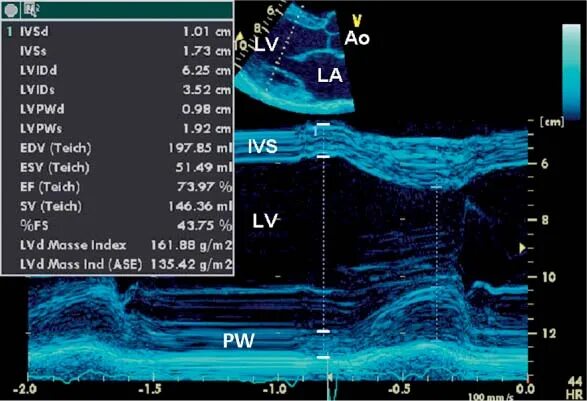

M mode